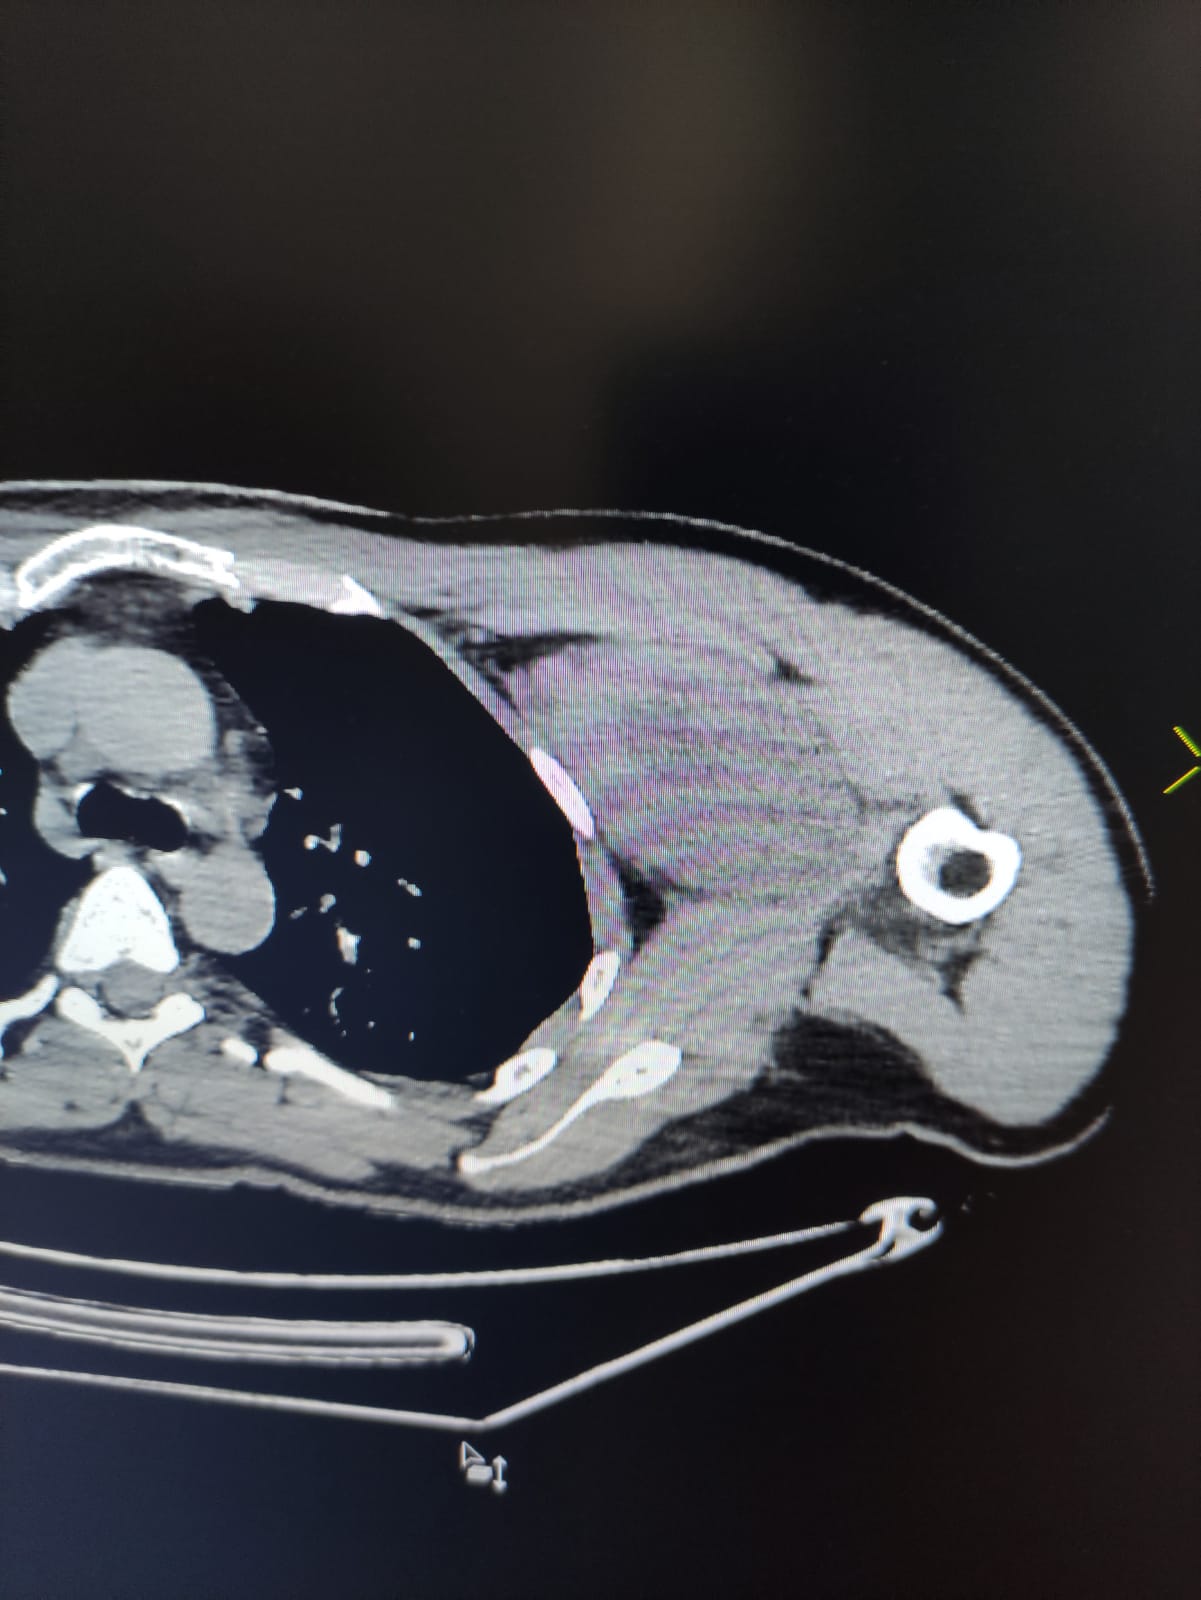

Уже при первичном осмотре заведующий кафедрой нейрохирургии СГМУ Андрей Чехонацкий выявил несоответствие симптомов диагнозу, с которым пациент был направлен на лечение. При осмотре в подмышечной области было обнаружено объемное образование плотно-эластической консистенции, воздействующее на ветви плечевого сплетения. Больному провели дополнительное обследование – МРТ, КТ правого плечевого пояса, допплерографию сосудов, электронейромиографию, что подтвердило результаты осмотра. Объемное образование располагалось в области со сложным анатомическим строением, воздействовало на нервы и сосуды, тесно взаимодействующие с мышцами грудного пояса. Не исключалась опухоль, исходящая из мышц, поэтому оперативное лечение решено было провести совместно с сотрудниками кафедры госпитальной хирургии.